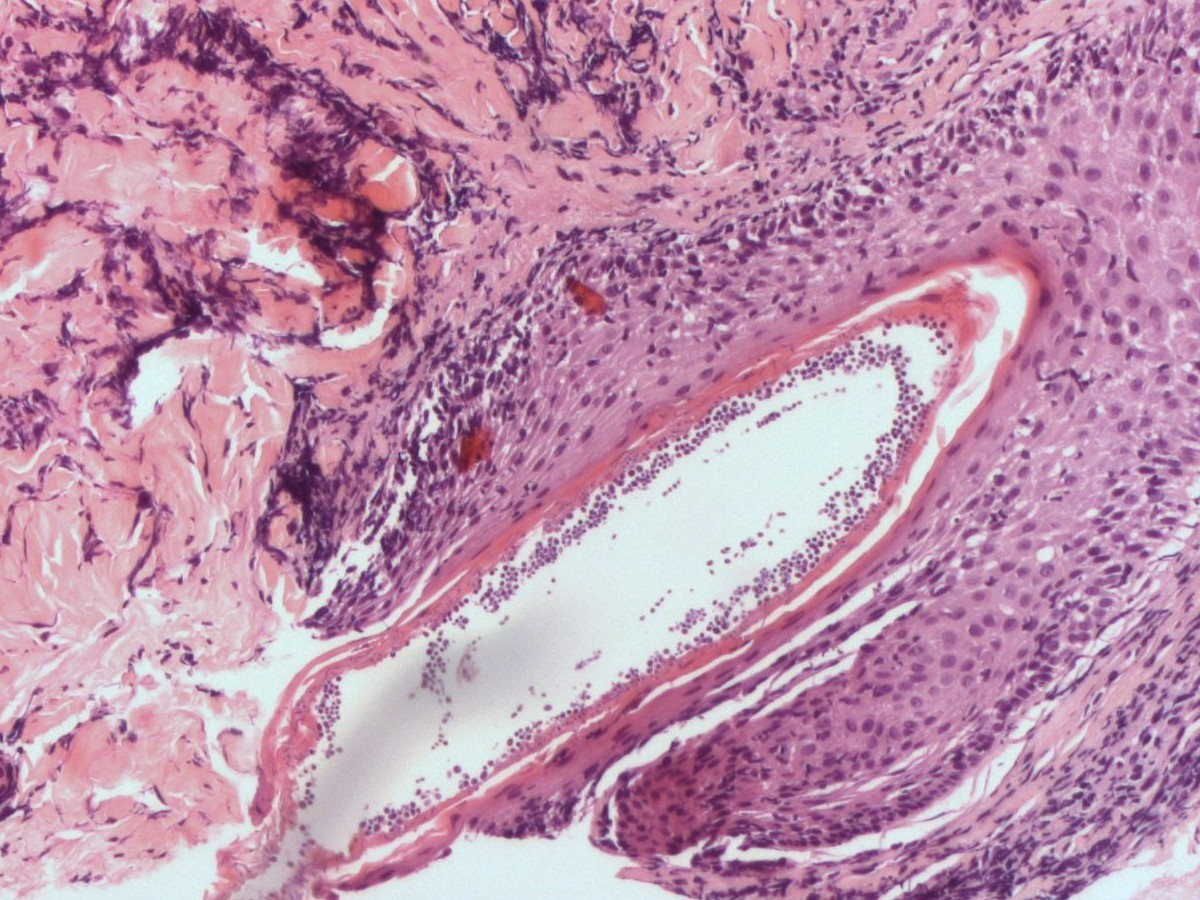

Ook een biopt kan de diagnose aantonen, hierbij zijn schimmeldraden en/of gistbolletjes

te zien in de haarfollikel (PAS kleuring). Bij oppervlakkige mycosen met randschilfering

![Histologie van dermatomycosis barbae, tinea barbae (click on photo to enlarge) [source: www.huidziekten.nl] Histologie van dermatomycosis barbae, tinea barbae](../../../images/dermatomycosis-barbae-PA-1z.jpg) |

![Histologie van dermatomycosis barbae, tinea barbae (click on photo to enlarge) [source: www.huidziekten.nl] Histologie van dermatomycosis barbae, tinea barbae](../../../images/dermatomycosis-barbae-PA-2z.jpg) |

![Histologie van dermatomycosis barbae, tinea barbae (click on photo to enlarge) [source: www.huidziekten.nl] Histologie van dermatomycosis barbae, tinea barbae](../../../images/dermatomycosis-barbae-PA-3z.jpg) |

| mycose

baardstreek (PA) |

mycose

![Histologie van dermatomycosis barbae, tinea barbae (click on photo to enlarge) [source: www.huidziekten.nl] Histologie van dermatomycosis barbae, tinea barbae](../../../images/dermatomycosis-barbae-PA-4z.jpg) |

![Histologie van dermatomycosis barbae, tinea barbae (click on photo to enlarge) [source: www.huidziekten.nl] Histologie van dermatomycosis barbae, tinea barbae](../../../images/dermatomycosis-barbae-PA-5z.jpg) |

![Histologie van dermatomycosis barbae, tinea barbae (click on photo to enlarge) [source: www.huidziekten.nl] Histologie van dermatomycosis barbae, tinea barbae](../../../images/dermatomycosis-barbae-PA-6z.jpg) |

PAS kleuring |